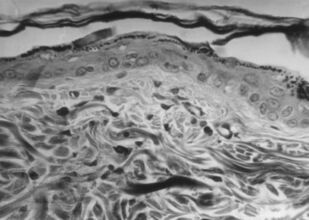

Лишай Видаля: экспериментальное и клиническое применение ультрафонофореза флюоцинолона ацетонида

Монография предназначена для врачей дерматовенерологов, физиотерапевтов, врачей общей практики, студентов выших медВУЗОВ для эффективного и обоснованного применения метода ультрафонофореза флюоцинолона ацетонида у пациентов с простым хроническим лишаем (лишаем Видаля, ограниченного или очагового нейродермита).